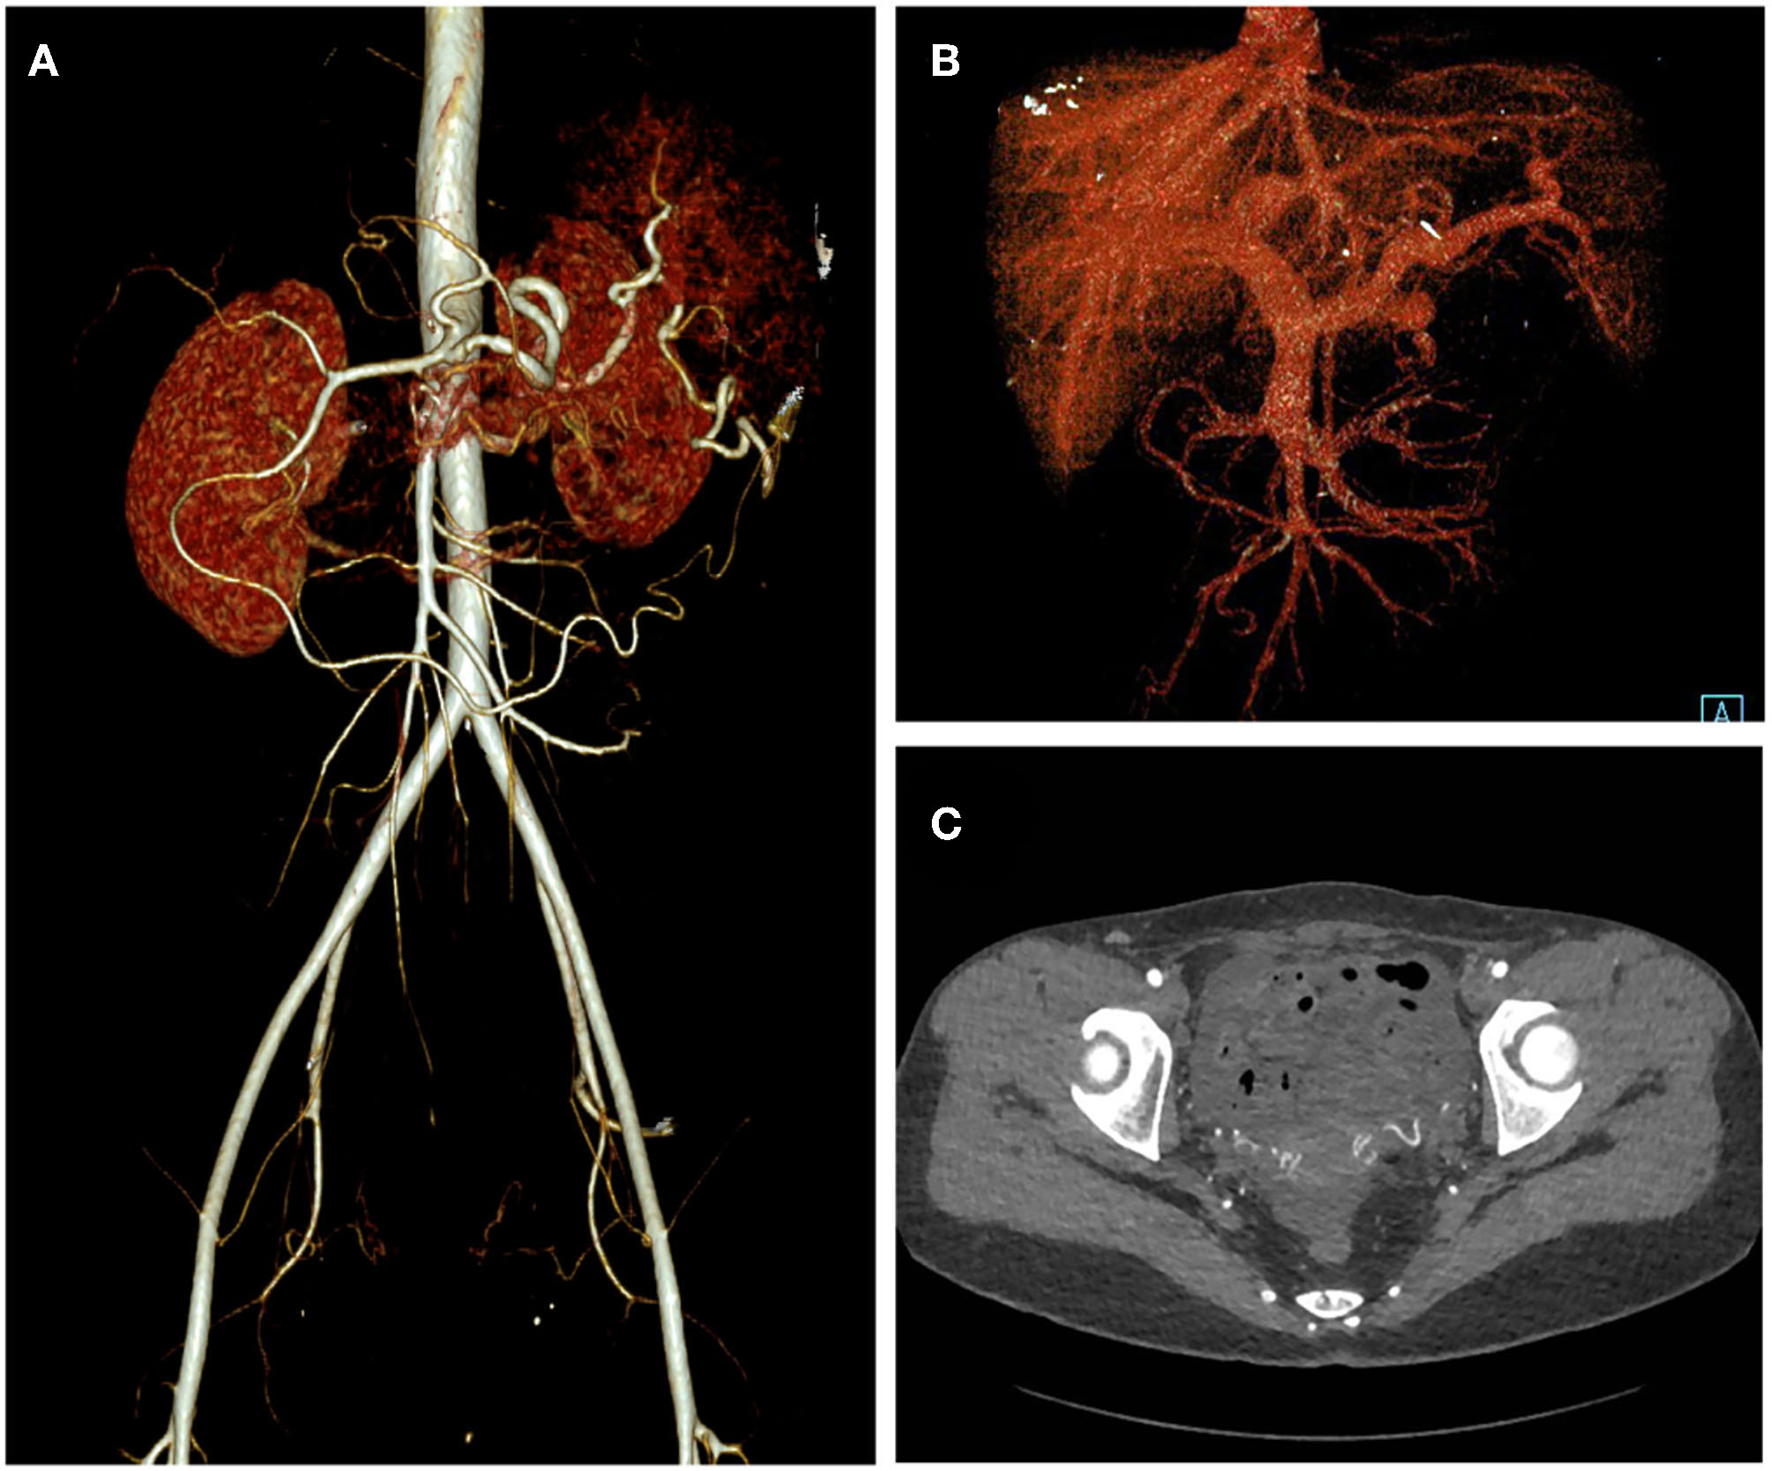

A 32-year-old woman was admitted to our center due to the finding of a pelvic mass with hypervascularity 2 years ago. She was generally asymptomatic and had no related family history. On physical examination, her mass was not palpable, but vascular bruits could be easily auscultated on the abdomen, especially in the peri-umbilicus area. The ultrasound revealed a pelvic mass with an abundant blood flow signal (Figure 1A). CT angiography (CTA) showed the nidus of pelvic arteriovenous malformation (AVM) and aneurysmal-dilated vessel (measured 72 × 56 mm) (Figure 1B). The 3D reconstruction of CTA demonstrated that the AVM had a single feeding artery originating from the splenic artery and two draining veins into the superior mesenteric vein, and then, a portal vein (Figure 2). Digital subtraction angiography (DSA) was used to further evaluate the AVM (Figures 3A–C). It was confirmed that the AVM finally drained into the portal vein and there were no other feeding arteries from bilateral internal iliac arteries (Supplemenatry Video 1). Considering the risk of aneurysm rupture and hemorrhage, the patient was treated with surgical resection of the AVM and ligation of the feeding artery and draining veins (Figure 3D). She recovered well after the operation and was discharged post-operatively on day 6. The 1-month follow-up CTA showed elimination of the abdominopelvic AVM (Figure 4) and the patient was doing well during the following 12 months.

Figure 2

3D reconstruction of CT angiography of the abdominopelvic arteriovenous malformation (AVM). (A) Arterial phase of CT angiography showed the AVM had a single feeding artery originating from the splenic artery. (B) Venous phase of CT angiography showed the AVM had two draining veins into the superior mesenteric vein and then the portal vein.

Figure 4

One-month post-operative CT angiography of the patient. Arterial phase (A), Venous phase (B), and axial view (C) of the CT angiography showed elimination of the abdominopelvic AVM.